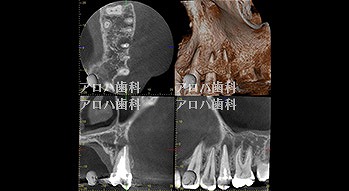

case4

再根管治療 2年予後

再根管治療の汚染の改善

破折器具除去もあり。

case5

左>頬側よりGP挿入。MB根尖の透過像と一致。P根にも透過像。穿孔を疑う。右>術後1年

左>術前

右>術後1年。

頬側の瘻孔

破折器具除去症例

case6

破折器具の除去 麻痺の恐れ

case7

MB根 湾曲の先に破折器具

器具の除去